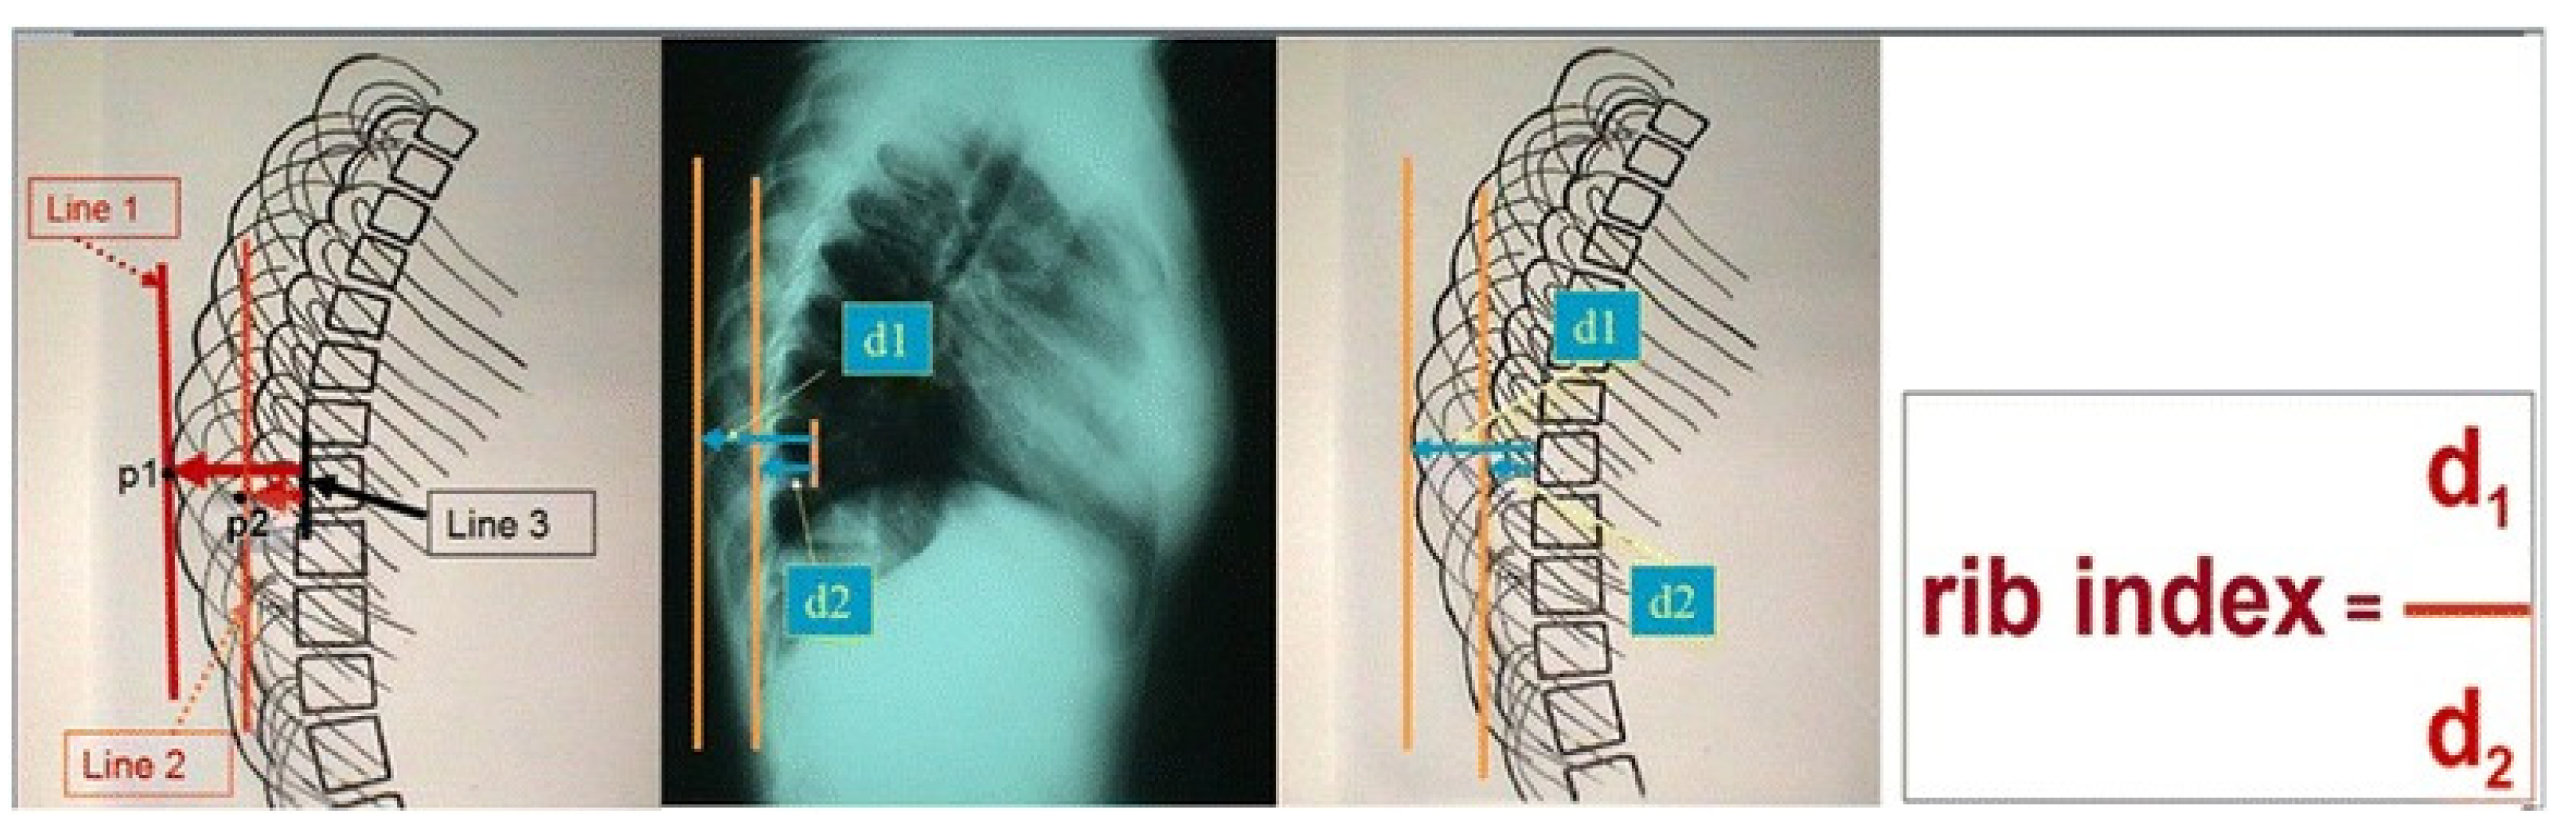

- Grivas, T.B. Rib index. Scoliosis 2014, 9, 20. [Google Scholar] [CrossRef]